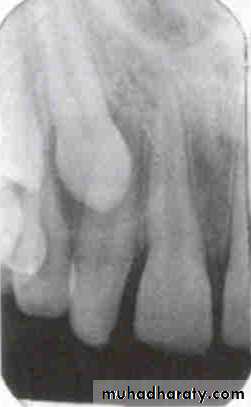

Is the composite restoration on tooth # 8 (arrows) located on the buccal or lingual?

canine filmincisor film

The restoration is located on the buccal. The tube head moves mesially from the canine film to the incisor film (x-ray beam projected more distally) and the composite moves distally, which is the opposite direction.